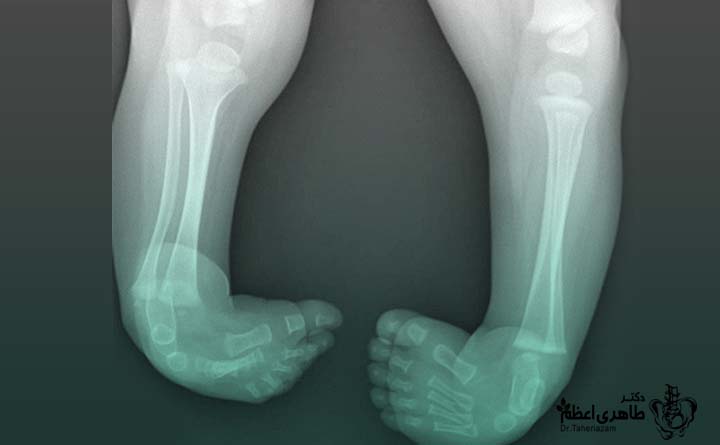

کلاب فوت که در پزشکی با عنوان Congenital Clubfoot شناخته میشود، یک ناهنجاری مادرزادی پا است که در آن پا در زمان تولد در وضعیت غیرطبیعی قرار دارد. در این حالت، پا معمولاً به سمت داخل و پایین چرخیده و شکل طبیعی خود را ندارد. این تغییر وضعیت فقط مربوط به استخوان نیست، بلکه عضلات، تاندونها و رباطهای پا نیز درگیر هستند.

پا چنبری از همان بدو تولد قابل مشاهده است و برخلاف برخی ناهنجاریها، در طول رشد بهوجود نمیآید. شدت آن میتواند از خفیف تا شدید متغیر باشد و ممکن است یک پا یا هر دو پا را درگیر کند. نکته مهم این است که این وضعیت بهخودیخود دردناک نیست، اما اگر درمان نشود، میتواند راه رفتن طبیعی کودک را مختل کند.

در کلاب فوت، ساختارهای نرم اطراف مچ و پا کوتاهتر و سفتتر از حالت طبیعی هستند. همین موضوع باعث میشود پا بهراحتی در وضعیت درست قرار نگیرد. بههمین دلیل، درمان این بیماری بیشتر روی اصلاح تدریجی موقعیت پا تمرکز دارد، نه صرفاً تغییر ظاهری آن.